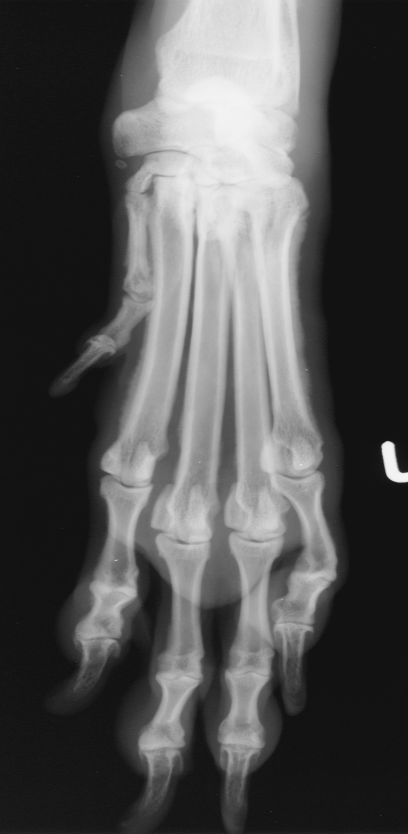

premature distal ulnar physis closure roentgen signs

gap - ulna and humerus, and gap at the bottom of ulna and carpus

cranial bowing of radius

which physis closed early